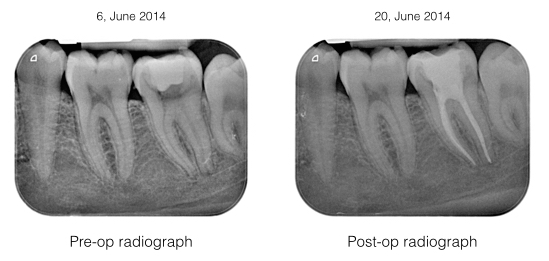

Examination: Lower left second molar has a gross decay. The tooth was very tender to percussion. There was no swelling noted. Tooth was painful to airblow. Intra-oral periapical radiography showed small periapical lesion on both mesial and distal root with widening of the lamina dura.

Diagnosis: Acute apical periodontitis on tooth 37

Treatment: Tooth 37 was anesthetized and filled. Root canal treatment (RCT) on tooth 37 was initiated under rubber dam isolation. Microscopic investigation did not reveal any fracture. All 3 canals were shaped, cleaned, dried and dressed with calcium hydroxide for a week. Tooth 37 was subsequently obturated up to full working length.